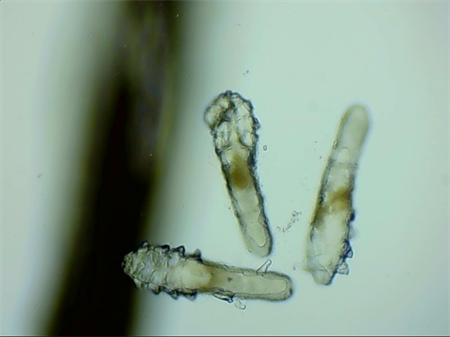

這就不得不提到眼科醫(yī)生經(jīng)常使用的螨蟲檢測工具——螨蟲鏡檢。它通過顯微利器,無死角全方位掃描你的睫毛,讓螨蟲無處遁形。

▲螨蟲鏡檢